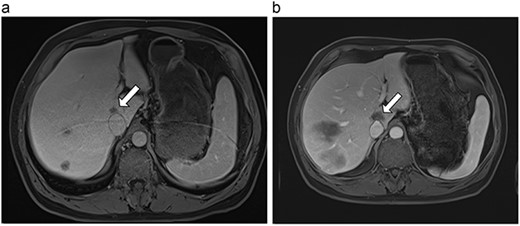

(a) Pre-ablation MRI demonstrating 14 mm lesion in caudate lobe of liver. (b) Post-ablation MRI (23 days postoperatively) demonstrating 23.8 mm complete ablation of caudate lesion.

| 4 (6a,b) | 51, M | Colon adenocarcinoma | 6 cycles FOLFOX | 4 | Laparoscopic microwave ablation | 14 | 23.8 | 9.8 | 13 | Yes |